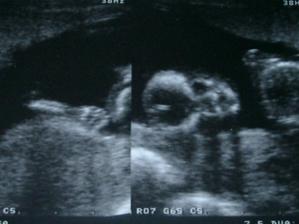

Príbeh Emky alebo Adamka 🙂

Asi budem Adamko, lebo instinktivne to tak mamina silno citi, ale uvidime casom, ci sa zo mna nevykluje Emka ;) ... a vyklul sa predsa Adamko!!! 😉 takze mamca to dobre citila!